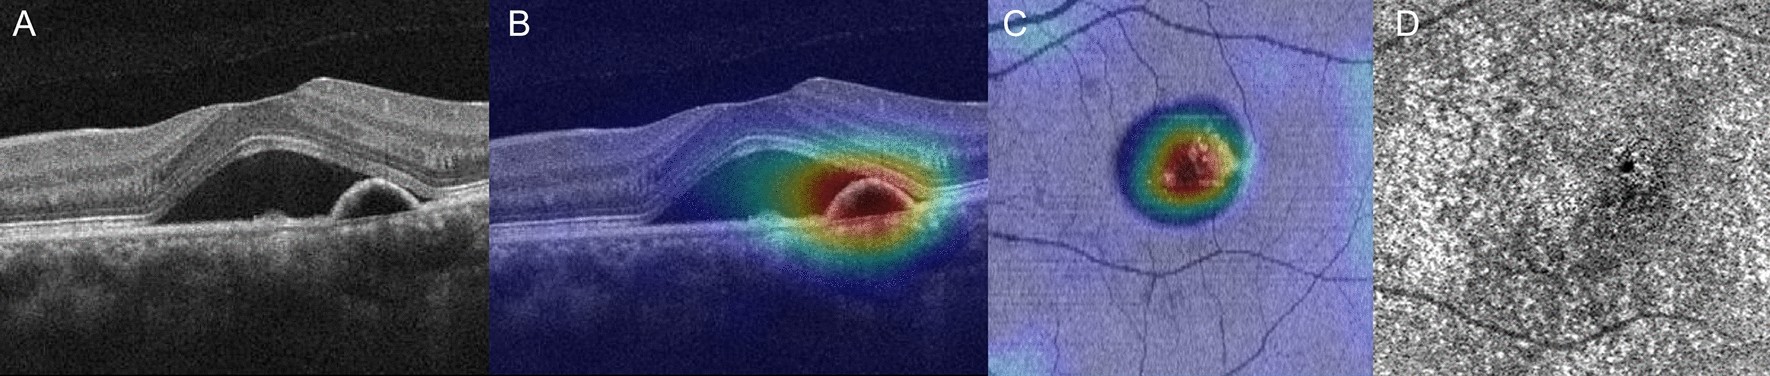

Figure 3

A representative case of persistent CSC with OCT angiography: the left eye of a 45-year-old male. (A) The OCT B-scan shows SRF with shallow irregular PED. (B) The heatmap overlying the OCT B-scan highlights important areas for use of DL in determining the prognosis of this case as persistent CSC. (C) A heatmap overlying the OCT en face image of the ellipsoid zone layer highlights the important areas. (D) OCT angiography does not reveal any choroidal neovascularization.